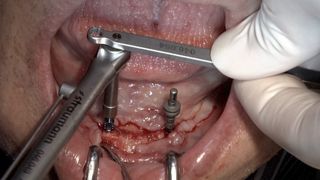

Implant surgery is similar to many other oral surgical procedures. It starts with appropriate preparation for the surgery. Like in other oral sur­gical interventions, working under sterile conditions is mandatory. Im­plant placement normally requires raising a soft tissue flap, preparing the implant beds by drilling the alveolar bone, placement of the im­plants and healing components, fol­lowed by adequate closure of the wound.

Know how to assess bone quality, perform an appropriate incision to raise a full-thickness flap and expose the bone.

Be able to place the implants in the correct three-dimensional position.